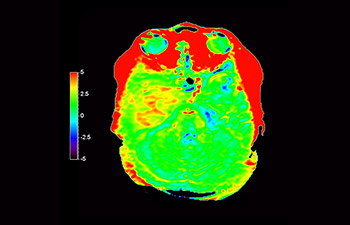

Brain lesion

with 3D APT